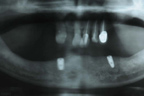

左下顎植入兩顆牙根。

X光片顯示植體位置。